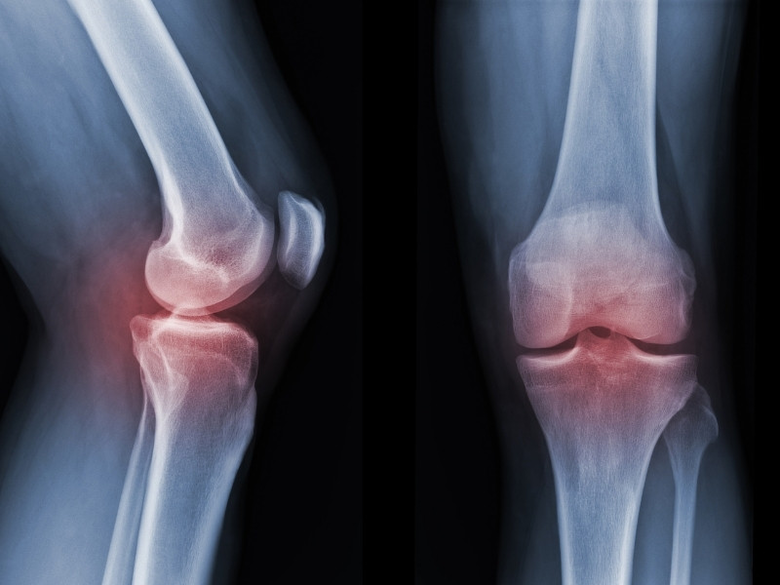

Çalışmaya ilişkin bilgiler veren Prof. Dr. Fırtına, kemik erimesinin dünya genelinde yaklaşık 200 milyon kişiyi olumsuz etkilediğini söyledi. Osteoporozun tedavisi için şu anda yan etkisi olmayan etkili bir ilacın bulunmadığını belirten Prof. Dr. Fırtına, "Osteoporoz, çoğu zaman sadece kemik yoğunluğundaki azalma olarak algılanıyor; oysa hastaların günlük yaşamında çok daha derin etkiler oluşturan bir tabloyla karşı karşıyayız. Bu hastalık, kişinin en basit hareketlerini bile çekinerek yapmasına neden olabiliyor. Yürümek, eğilmek, eşya taşımak ya da tek başına dışarıya çıkmak gibi sıradan görülen davranışlar, zamanla ciddi bir kaygı kaynağına dönüşebiliyor. Kırık riskiyle yaşamak, hastalarda yalnızca fiziksel değil, duygusal ve sosyal açıdan da önemli bir yük oluşturuyor" diye konuştu.